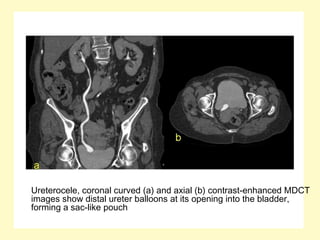

Ureterocele, coronal curved (a) and axial (b) contrast-enhanced MDCT

images show distal ureter balloons at its opening into the bladder,

forming a sac-like pouch

Ureterocele, coronal curved(a) and axial (b) contrast-enhanced MDCT images show distal ureter balloons at its opening into the bladder, forming a sac-like pouch